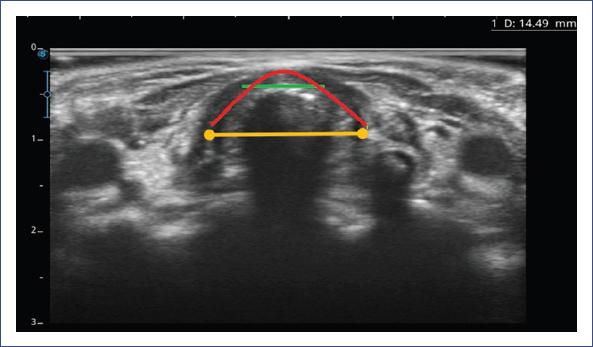

El IPFS y el LACWD se midieron con ultrasonido portátil Sonoscape E2 y transductor lineal (7-15 mHz) usando una configuración para tejidos blandos. Dicha medición se realizó por un intensivista pediatra ecografista crítico durante el protocolo de retiro del ventilador. Se obtuvieron tres mediciones y se promediaron. Las estructuras que se visualizan en la ecografía laríngea se muestran en la figura 1. La técnica de medición del IPFS se explica en la figura 2, y la medición del LACWD se explica en las figuras 3 y 4.

Figura 3 Medición del ancho de la columna de aire laríngea con globo inflado. Con el paciente en decúbito supino y el cuello en hiperextensión, se coloca el transductor en orientación transversal sobre la membrana cricotiroidea, obteniendo una imagen transversa de la laringe, las cuerdas vocales verdaderas, el cartílago tiroides y los cartílagos aritenoides. La diferencia del ancho de la columna de aire laríngea (línea amarilla) se define como la diferencia entre el ancho de la columna de aire a través de las cuerdas vocales medido transversalmente con el globo de la cánula inflado.

Figura 4 Medición del ancho de la columna de aire laríngea con el globo desinflado.